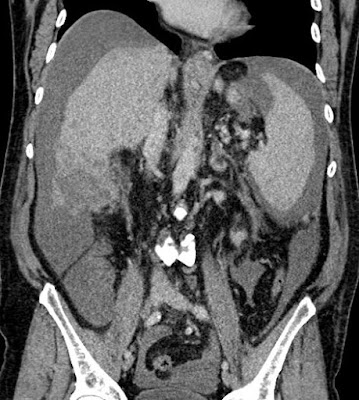

Cirrhosis talaján kialakult hepatocellularis carcinoma Szerző: admin | jan 20, 2011 | Focal liver lesions | Nincsenek hozzászólások cirrhosis, apró góc a VIII segmentumban, ascites a májban látható malignus góc részben necroticus, a májfelszínt áttörte